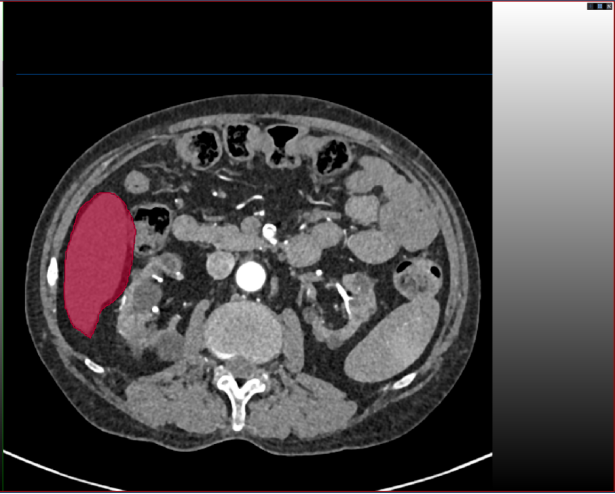

标注示例

下面我进行标注一层进行展示,以更快学习使用,还是分步骤实现吧!(以标注肝脏为例子)

Step 1:点击标注工具add

Step 2:沿着标注目标边缘勾勒

以看到我的勾勒超出肝脏区域了,此外标注的颜色太浓会影响我对标注边界的判断。所以需要对标注进行:1)淡化标注颜色;2)修改标注。